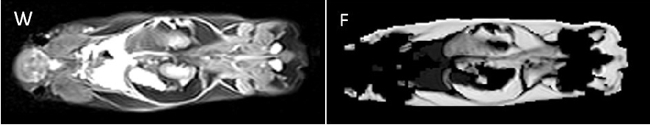

b) Small Animal MRI

In addition to clinically oriented projects, the Department of Radiology conducts experimental MR examinations on various animal models and specimens. Over the years, coil setup and imaging sequences have been optimised accordingly. Study topics include: mouse spinal cord imaging after shock wave treatment to promote spinal cord repair; volumetry of mouse myocardium to quantify fibrotic changes after constriction of the aorta and pulmonary artery; volumetry of the mouse brain to quantify fixation shrinkage; pulse wave velocity imaging in rabbits to evaluate aortic plaques; volumetric quantification of subcutaneous and visceral fat in mice on different diets; detection of intervertebral disc herniation in knockout mice.